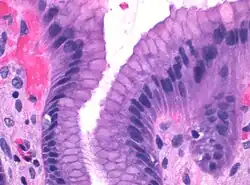

![]() Microscopic section of gastric mucosa. Foveolar cells can be seen at top of the image lining the surface and pits | |

Foveolar cells or surface mucous cells are mucus-producing cells which cover the inside of the stomach, protecting it from the corrosive nature of gastric acid.[1][a] These cells line the gastric mucosa and the gastric pits. Mucous neck cells are found in the necks of the gastric glands. The mucus-secreting cells of the stomach can be distinguished histologically from the intestinal goblet cells, another type of mucus-secreting cell.

Foveolar cells line the surface of the stomach and the gastric pits. They constitute a simple columnar epithelium, as they form a single layer of cells and are taller than their width. Other mucus-secreting cells are the mucous neck cells in the necks of the gastric glands.[2]: 257